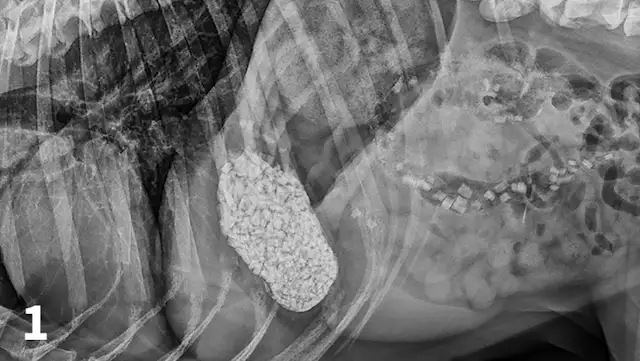

CBC reveals a leukocytosis (19.34 103/L; range, 5.10-14.00) characterized by a lymphocytosis (5.5 103/L; range, 1.4-4.6) and a mature neutrophilia (13.10 103/L; range, 2.65-9.80) with a mild thrombocytopenia (171 103/L; range, 147-243). A pancreatic-specific lipase is elevated (580 g/L; range, 0-200 g/L) and consistent with pancreatitis. Abdominal radiographs (Figures 1-3; See below) reveal a moderately distended stomach that contains a large number of irregularly shaped mineral opacities. Additional mineral opacities are present in multiple small intestinal segments as well as the colon. There is also a mild decrease in serosal detail in the mid-abdominal region.

Abdominal radiographs, repeated 14 hours later, reveal minimal aboral movement of the mineral opacities (Figures 4 and 5; see below).

A right lateral abdominal radiograph taken approximately 24 hours after glass ingestion. Multiple, irregularly shaped mineral opacities are present within the stomach, small intestine, and colon.